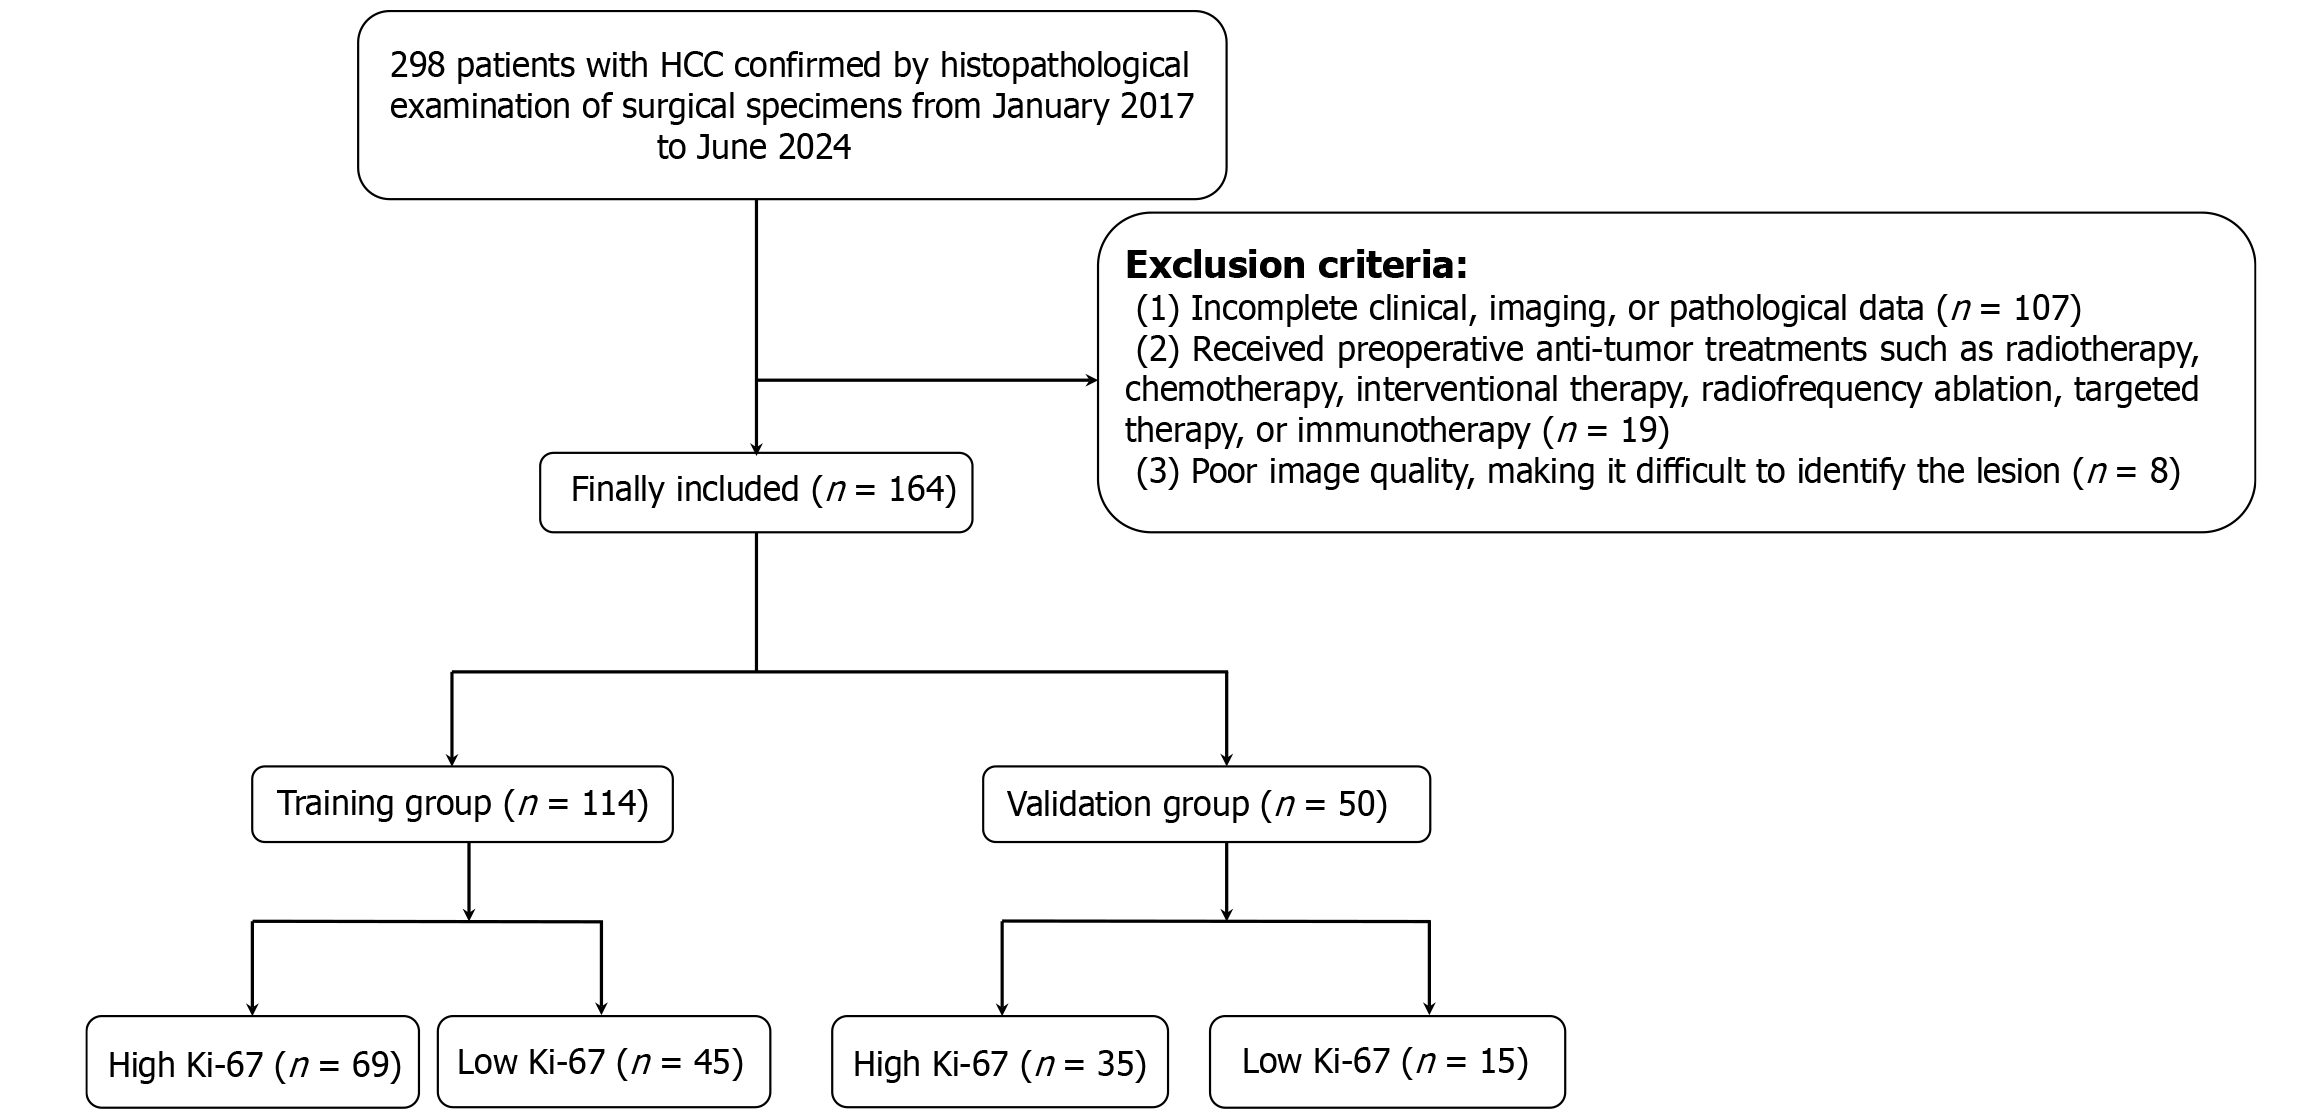

This study was approved by the Ethics Committee of the General Hospital of Northern Theater Command, No. Y(2024)168. Owing to the retrospective nature of the study and the use of anonymized data, there was no potential risk to the patients involved. Thus, informed consent was not necessary. Data were collected from 298 patients with HCC between January 2017 and June 2024. The inclusion criteria were: (1) Underwent enhanced liver CT scans within one month before surgery; (2) Aged ≥ 18 years; (3) Pathology report indicating a clear Ki-67 PI; and (4) Pathologically confirmed HCC. The exclusion criteria were: (1) Incomplete clinical, imaging, or pathology data (n = 107); (2) Received radiotherapy, chemotherapy, interventional therapy, radiofrequency ablation, targeted therapy, or immunotherapy before surgery (n = 19); or (3) Poor image quality, making it difficult to identify the lesion (n = 8). Ultimately, 164 patients with HCC were included in the retrospective study and were randomly divided into a training group (n = 114) and a validation group (n = 50) at a 7:3 ratio. As shown in Figure 1, a flowchart detailing the inclusion and exclusion process of patients is presented.